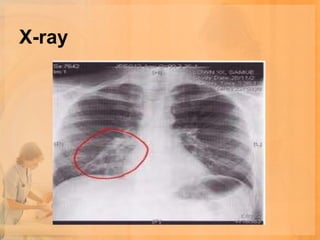

X-ray

• Chest x ray

Blood tests